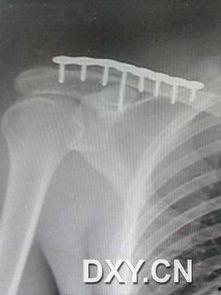

1. X光片上的“伤痕累累”:当你看到X光片上的锁骨,你会发现它就像被刀割过一样,断裂的地方清晰可见。

3. 手术后的“伤痕累累”:手术后的锁骨韧带断裂图片更是让人心疼,断裂的韧带被缝合在一起,虽然已经尽力修复,但痕迹依然明显。